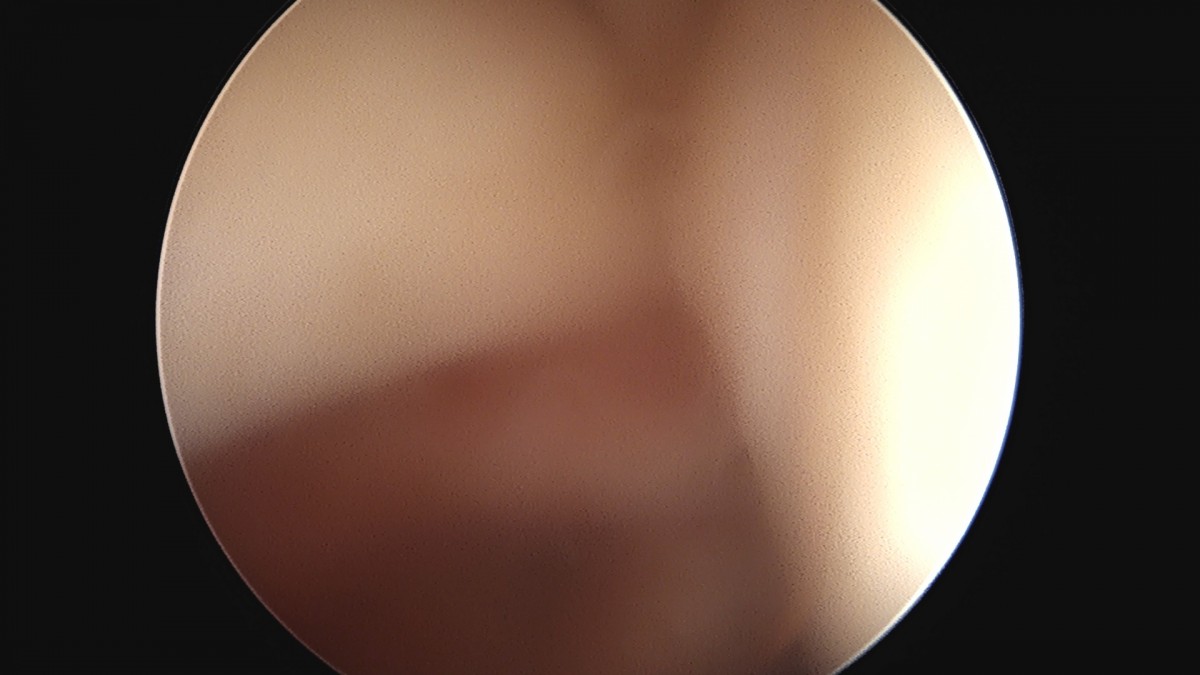

이재상원장님 어깨 견봉하 감압술 김선O 환자

dae765e4d9ac96aee867c9d6292d8784_1758004050_0559.jpg